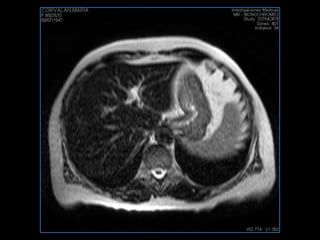

PROTOCOLO hígado graso AXIAL in phase y out phase AX T1 y AX fat sat +SAG T2  CON   GADOLINIO :  COR T1+AX T1(DIN) SAT: NO  FASE: RL THK: 4MM  COIL:  GAP: (FACTOR 1.4)  FOV: 40 CM NEX:2 SINCRONIZACION RESPIRATORIA EN 3 O 4 CICLOS ALE

PROTOCOLO hemocromatosis AXIAL supresión grasa /AX multieco en higado COR T2 AX T1 +SAG T2  CON   GADOLINIO :  COR T1+AX T1 SAT: NO  FASE: RL THK: 4MM  COIL:  GAP: (FACTOR 1.4) 1MM FOV: 40 CM NEX:2 SINCRONIZACION RESPIRATORIA EN 3 O 4 CICLOS ALE